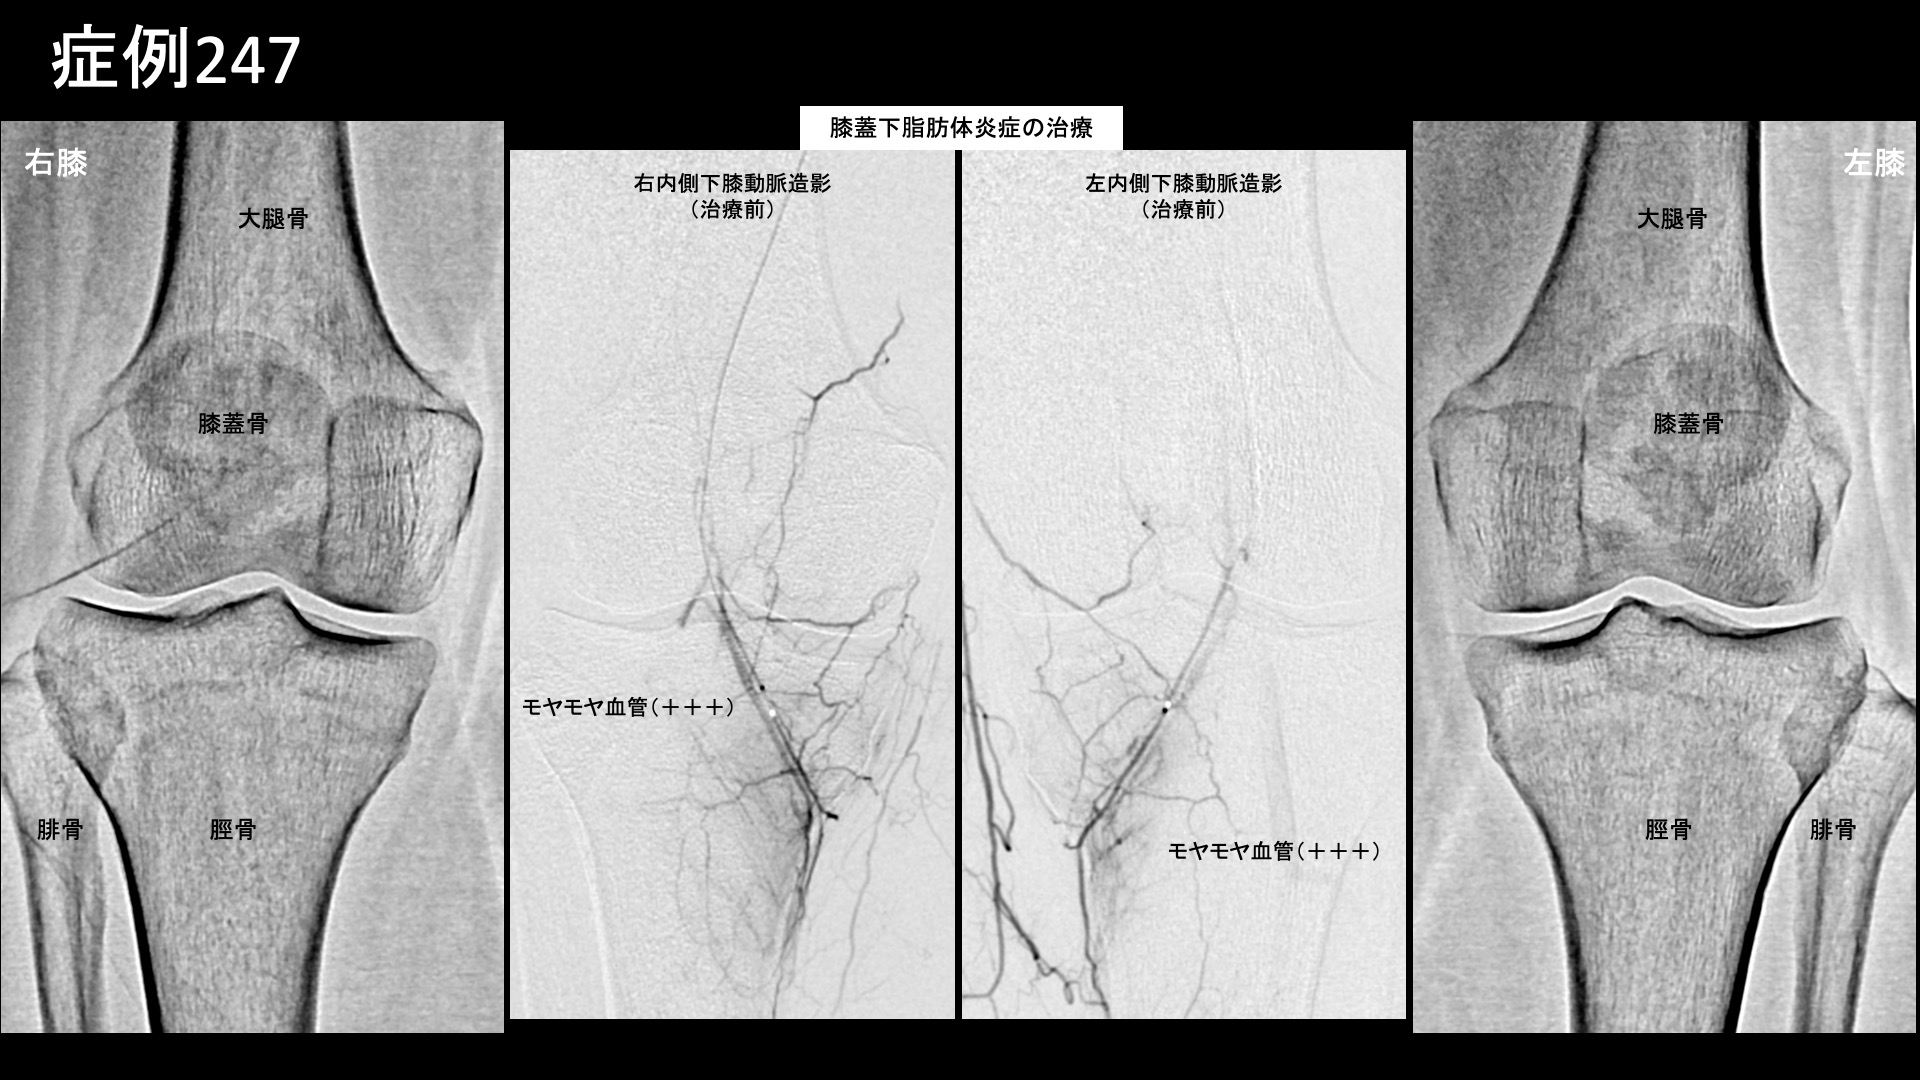

膝:変形性膝関節症など 【50代:女性】長い距離を歩くと痛くなる、登山家に生じた両膝の痛みに対するモヤモヤ血管治療(膝蓋下脂肪体炎、腸脛靭帯炎) 2025.11.05 鴨井院長による動画解説 受診までの経過 日常的に登山をされる方です。10年前に階段で転落してコンクリートの地面に両膝を打撲したことがありました。以前から、登山下山時に両膝が少し痛くなることがありましたが、1年半前頃に3-4時間程度の登山後に強い痛みがあったため、整形外科を受診しました。MRI検査の結果、軟骨の磨り減りはほとんど無く、膝蓋下脂肪体炎が疑われると言われました。2km以上歩くと痛くなり、その後2-3週間すると痛みが無くなります。3km以上になると、激痛になります。左右差は特にありませんでした。常に激痛があるわけではないものの、段々と歩ける距離が減ってきているため当院を受診されました。 診察時の所見 レントゲン、エコー検査とも変形性膝関節症の所見はありませんでした。膝蓋下脂肪体では、軽度の圧痛を認めました。MRIでも明らかな強い炎症ではありませんでしたが、両側膝蓋下脂肪体炎として矛盾せず、症状の性状からも治療による改善が期待されたため、モヤモヤ血管(病的新生血管)に対する運動器カテーテル治療(微細動脈塞栓術)を受けていただきました。 治療の所見 血管造影を行うと、両側の内側下膝動脈において、膝蓋下脂肪体に一致してモヤモヤ血管が濃染像として描出されました。更に左外側上膝動脈造影では、より豊富にモヤモヤ血管が濃染像として描出されました。術前の画像診断では明確ではありませんでしたが、症状の成因や、性状、この血管造影所見からは腸脛靭帯炎(代表的な、膝の外側の痛みの原因の一つ。別名ランナー膝。)の様相を呈していました。腸脛靭帯炎も合併していたのではないかと考えられます。治療後モヤモヤ血管は画像上速やかに消失しました。その他複数箇所の治療を行い終了しました。 治療前画像:損傷を受ける、あるいは繰り返しのストレスにより発生した異常な新生血管 治療後画像:カテーテルを用いて塞栓物質を血管内に投与し新生血管を塞いだ状態 治療費用:治療する部位によって費用が異なりますのでこちらをご参照ください。 主なリスク・副作用等:針を刺した場所が出血により腫れや痛みを生じたり、感染したりすることがあります(穿刺部合併症)。造影剤によるアレルギー(皮膚のかゆみ・赤み・息苦しくなるなどの症状)が出ることがあります。 治療後の経過 元々、少し長めに歩かなければ激痛は生じないため、治療後1ヶ月の直前に長めに歩いてみてもらいました。激痛は全く無く、階段を降りる際も、以前は他人の手を借りなければならなかったのが不要となっていました。まだ、熱い感じがしたり、それとは別に鈍い痛みを感じたりすることはありました。その後も順調に経過されたため、(良いことですが)受診はそれきりとなりました。追跡調査では、治療後3ヶ月時点で痛みは元の1/10程度、治療後6ヶ月ではほとんど痛みがゼロとなり、熱を持った感じも無くなりました。酷使して疲労が蓄積したときには鈍い痛みが出ることはありますが、それでも元の1/10程度とのことでした。膝蓋下脂肪体炎は比較的しつこい痛みの一つであり、完治するには少し時間がかかる傾向がありますが、ここまでくれば安心できます。無理のない範囲で登山を楽しんでいただければと思います。 膝蓋下脂肪体炎の詳細はこちら 【60代:女性】10年苦しんだ頭痛。考えがまとまらなくなり、家事もままならず。モヤモヤ血管治療により日常生活を取り戻すことができた実際の症例(筋緊張性頭痛、首肩こり、顎関節症) 前の記事 【60代:男性】痛くてドアノブも回せない、5年以上続いた手首の痛み。腱鞘炎に変形性手関節症を合併した一例(尺側手根伸筋腱の腱鞘炎、変形性手関節症、ドゥケルバン腱鞘炎) 次の記事